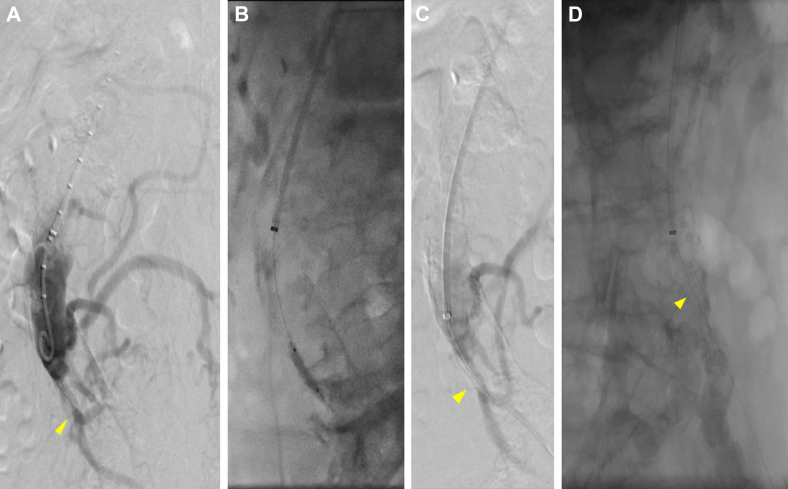

Fig 3.

A, Preoperative flush aortogram of patient 3 showing severe inferior mesenteric artery (IMA) stenosis (arrowhead) and distal filling of a prominent meandering mesenteric artery. B, Balloon angioplasty. C, Residual stenosis (arrowhead). D, Stent placement without visible stenosis (arrowhead).

Patient 3

A 77-year-old male patient with chronic postprandial abdominal pain and weight loss had presented with a 10-day history of acute exacerbation of pain with additional nausea. He had a lactate level of 3.5 mmol/L, and CTA demonstrated calcified occlusions of the celiac artery and SMA with high-grade IMA stenosis and a chronic-appearing infrarenal aortic occlusion. The patient was resuscitated and underwent urgent mesenteric angiography via a left brachial approach, which again demonstrated the celiac artery and SMA occlusions. The IMA was stenotic but patent, providing collateral flow to the mesentery and bilateral lower extremities. The IMA was stented with significant angiographic improvement seen (Fig 3).